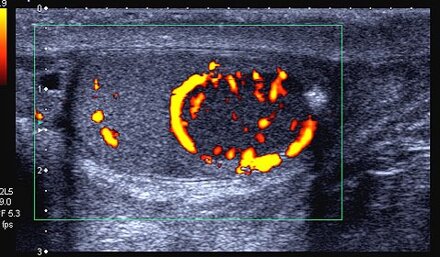

La diagnosi del tumore viene effettuata tramite unaecografia dello scroto e il dosaggio di alcuni marcatori, cioè sostanze presenti nel sangue prodotte dalle cellule tumorali o indotte dalla presenza del tumore. Tali marcatori sono la alfa-fetoproteina e la beta-HCG e la lattiodeidrogenasi (LDH).